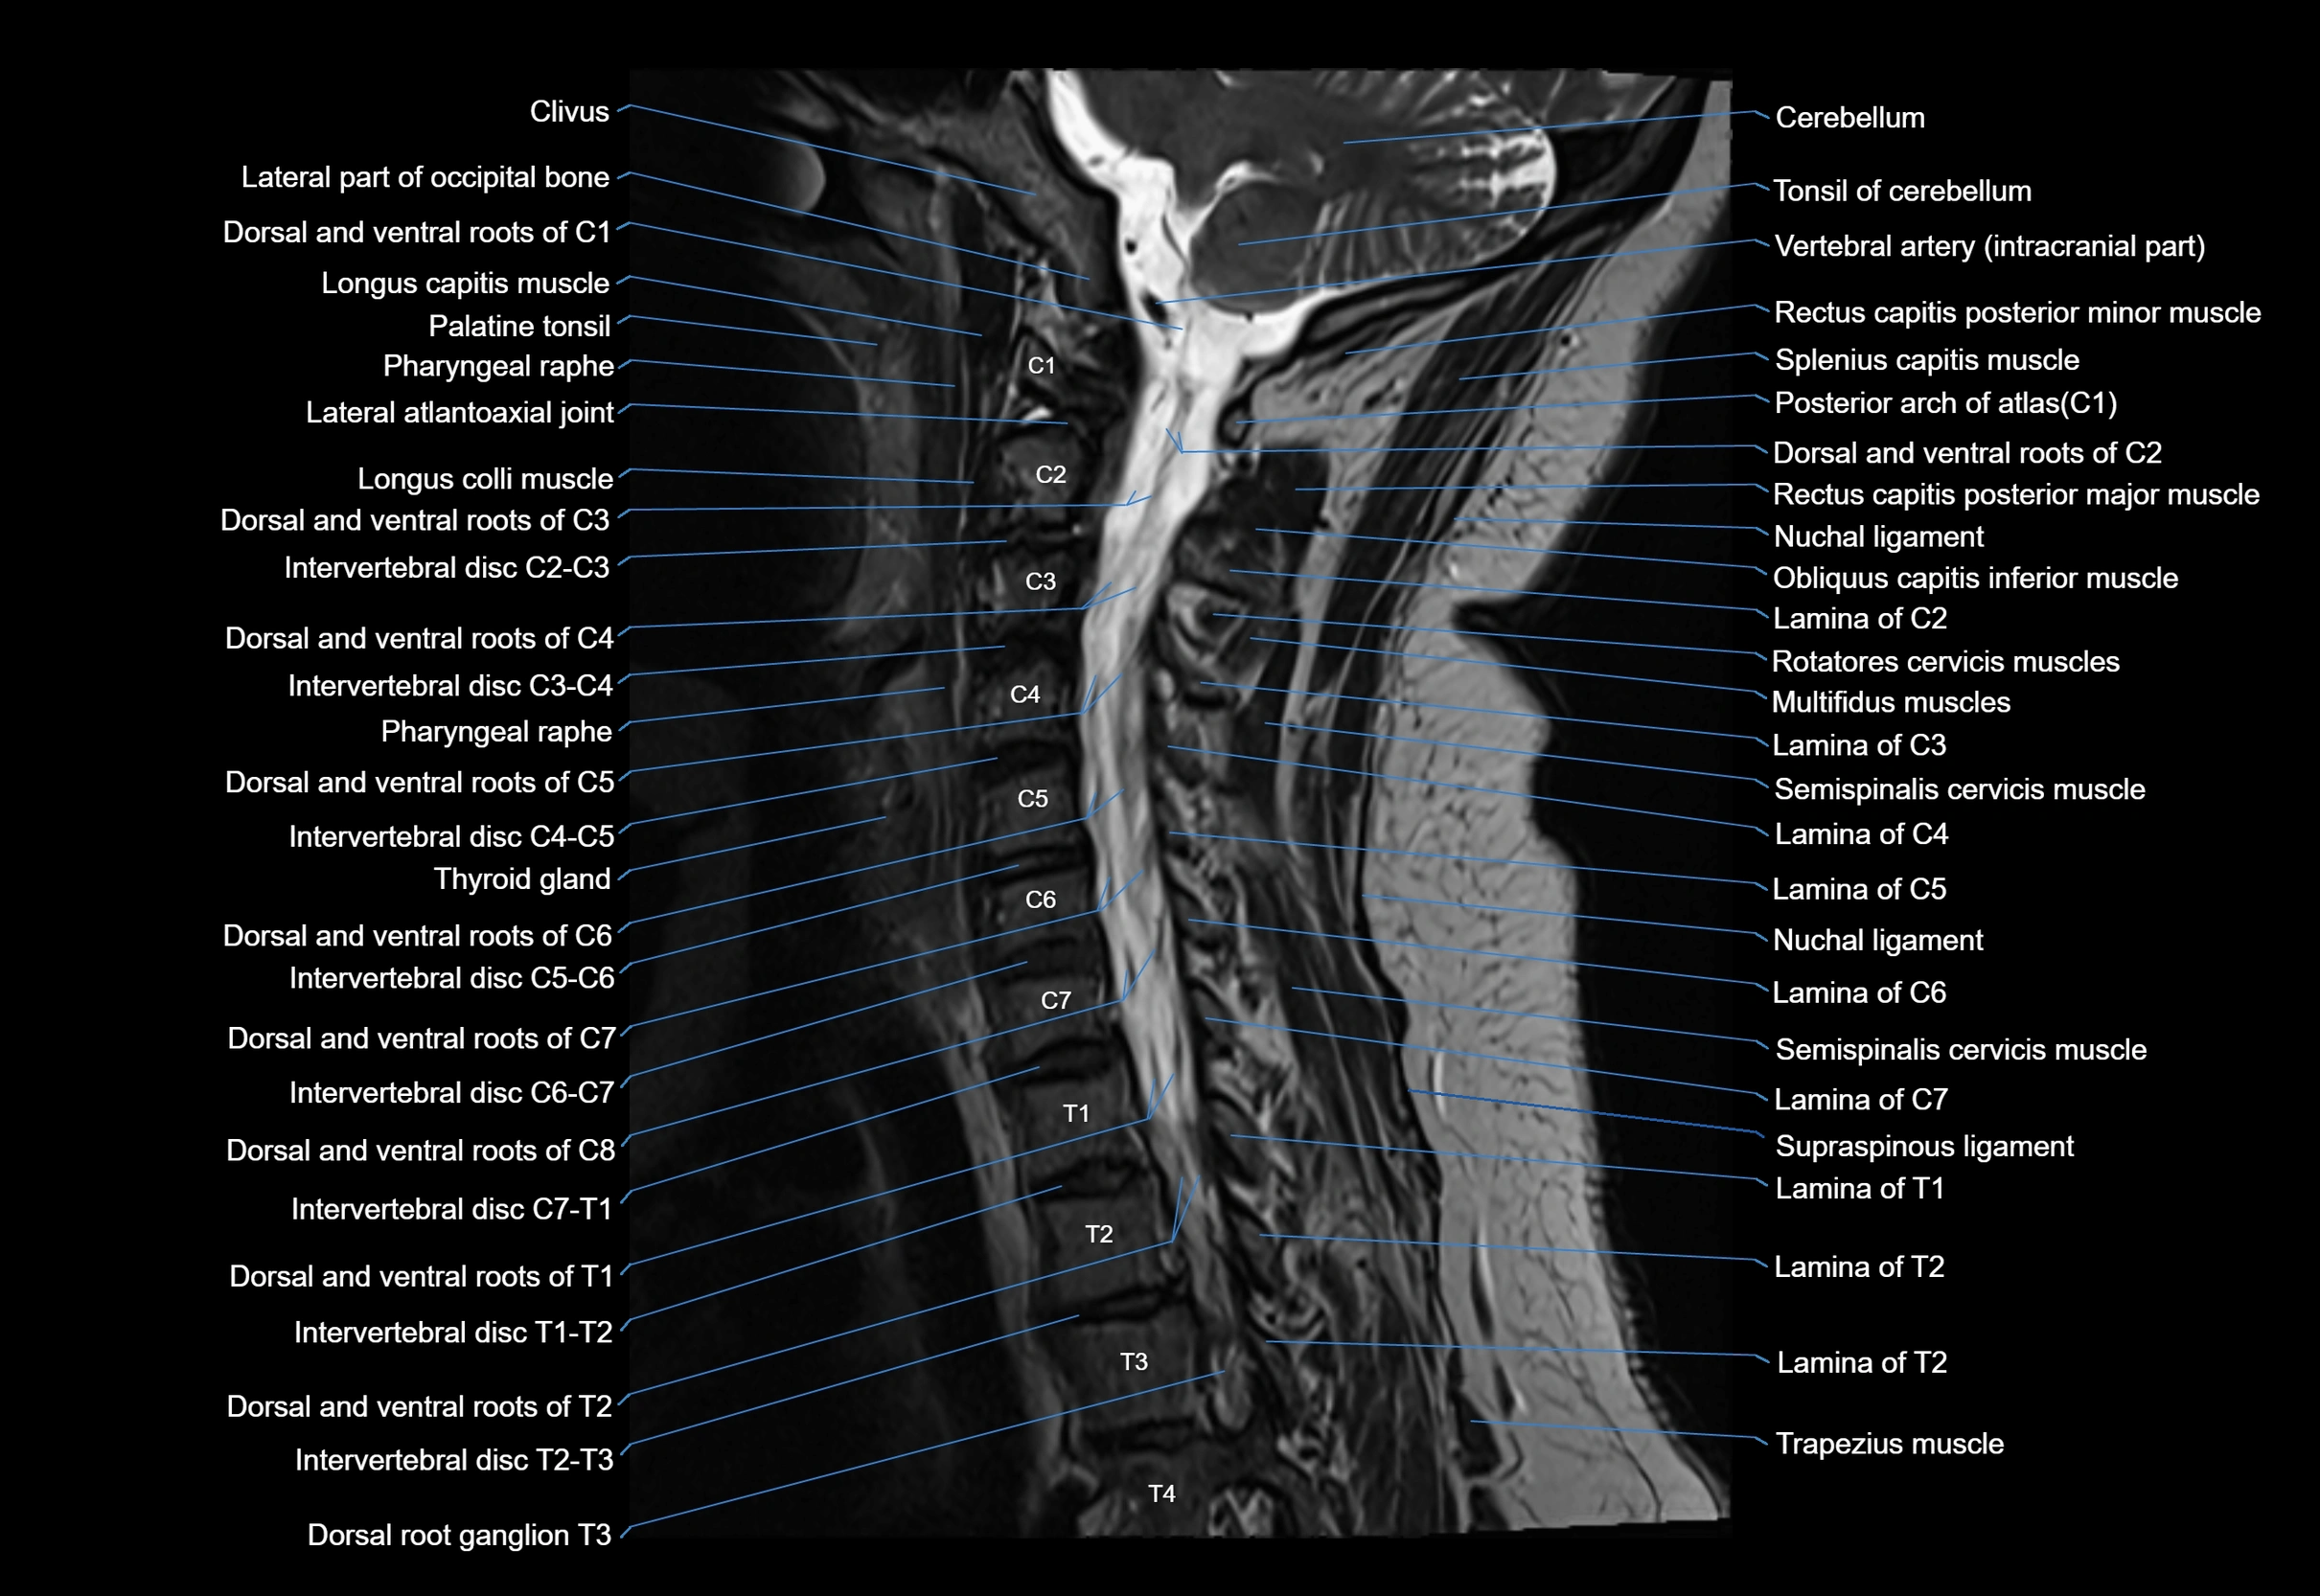

MRI appearance

T1-weighted images:

• Annular epiphysis: Low signal cortical rim at the vertebral margin

• Adjacent marrow: Intermediate-to-high signal in the vertebral body

• Disc interface: Clear delineation between bone and annulus

T2-weighted images:

• Annular epiphysis: Low signal intensity line

• Endplate cartilage (in younger patients): Intermediate signal

• Intervertebral disc: High signal nucleus pulposus

STIR:

• Annular epiphysis: Low signal cortical rim

• Adjacent marrow: Suppressed fat signal with preserved bony outline

• Utility: Highlights marrow and endplate interface in developing spine

MRI image

image